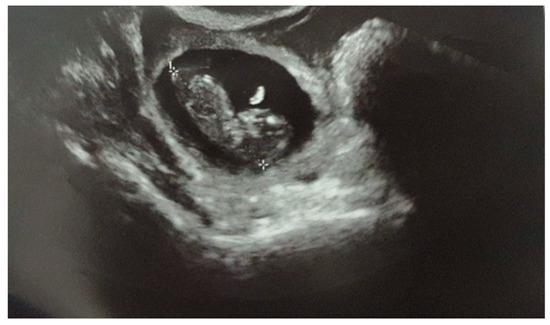

Due to the clinical course, the gestational age, and the size of the ectopic pregnancy, it was decided to take a surgical approach. The laparoscopic evaluation showed 700 mL of hemoperitoneum and an intact but swollen and bleeding right tuba, on the verge of breaking at the level of the ampulla (Figure 2). Right salpingectomy was performed, and the specimen removed was sent for histological examination. The exam confirmed the diagnosis of ectopic pregnancy with embryonic residues and chorionic villi compatible with the first trimester of pregnancy.

Figure 2. VLS image of the salpinx enlarged and bleeding due to ectopic pregnancy.